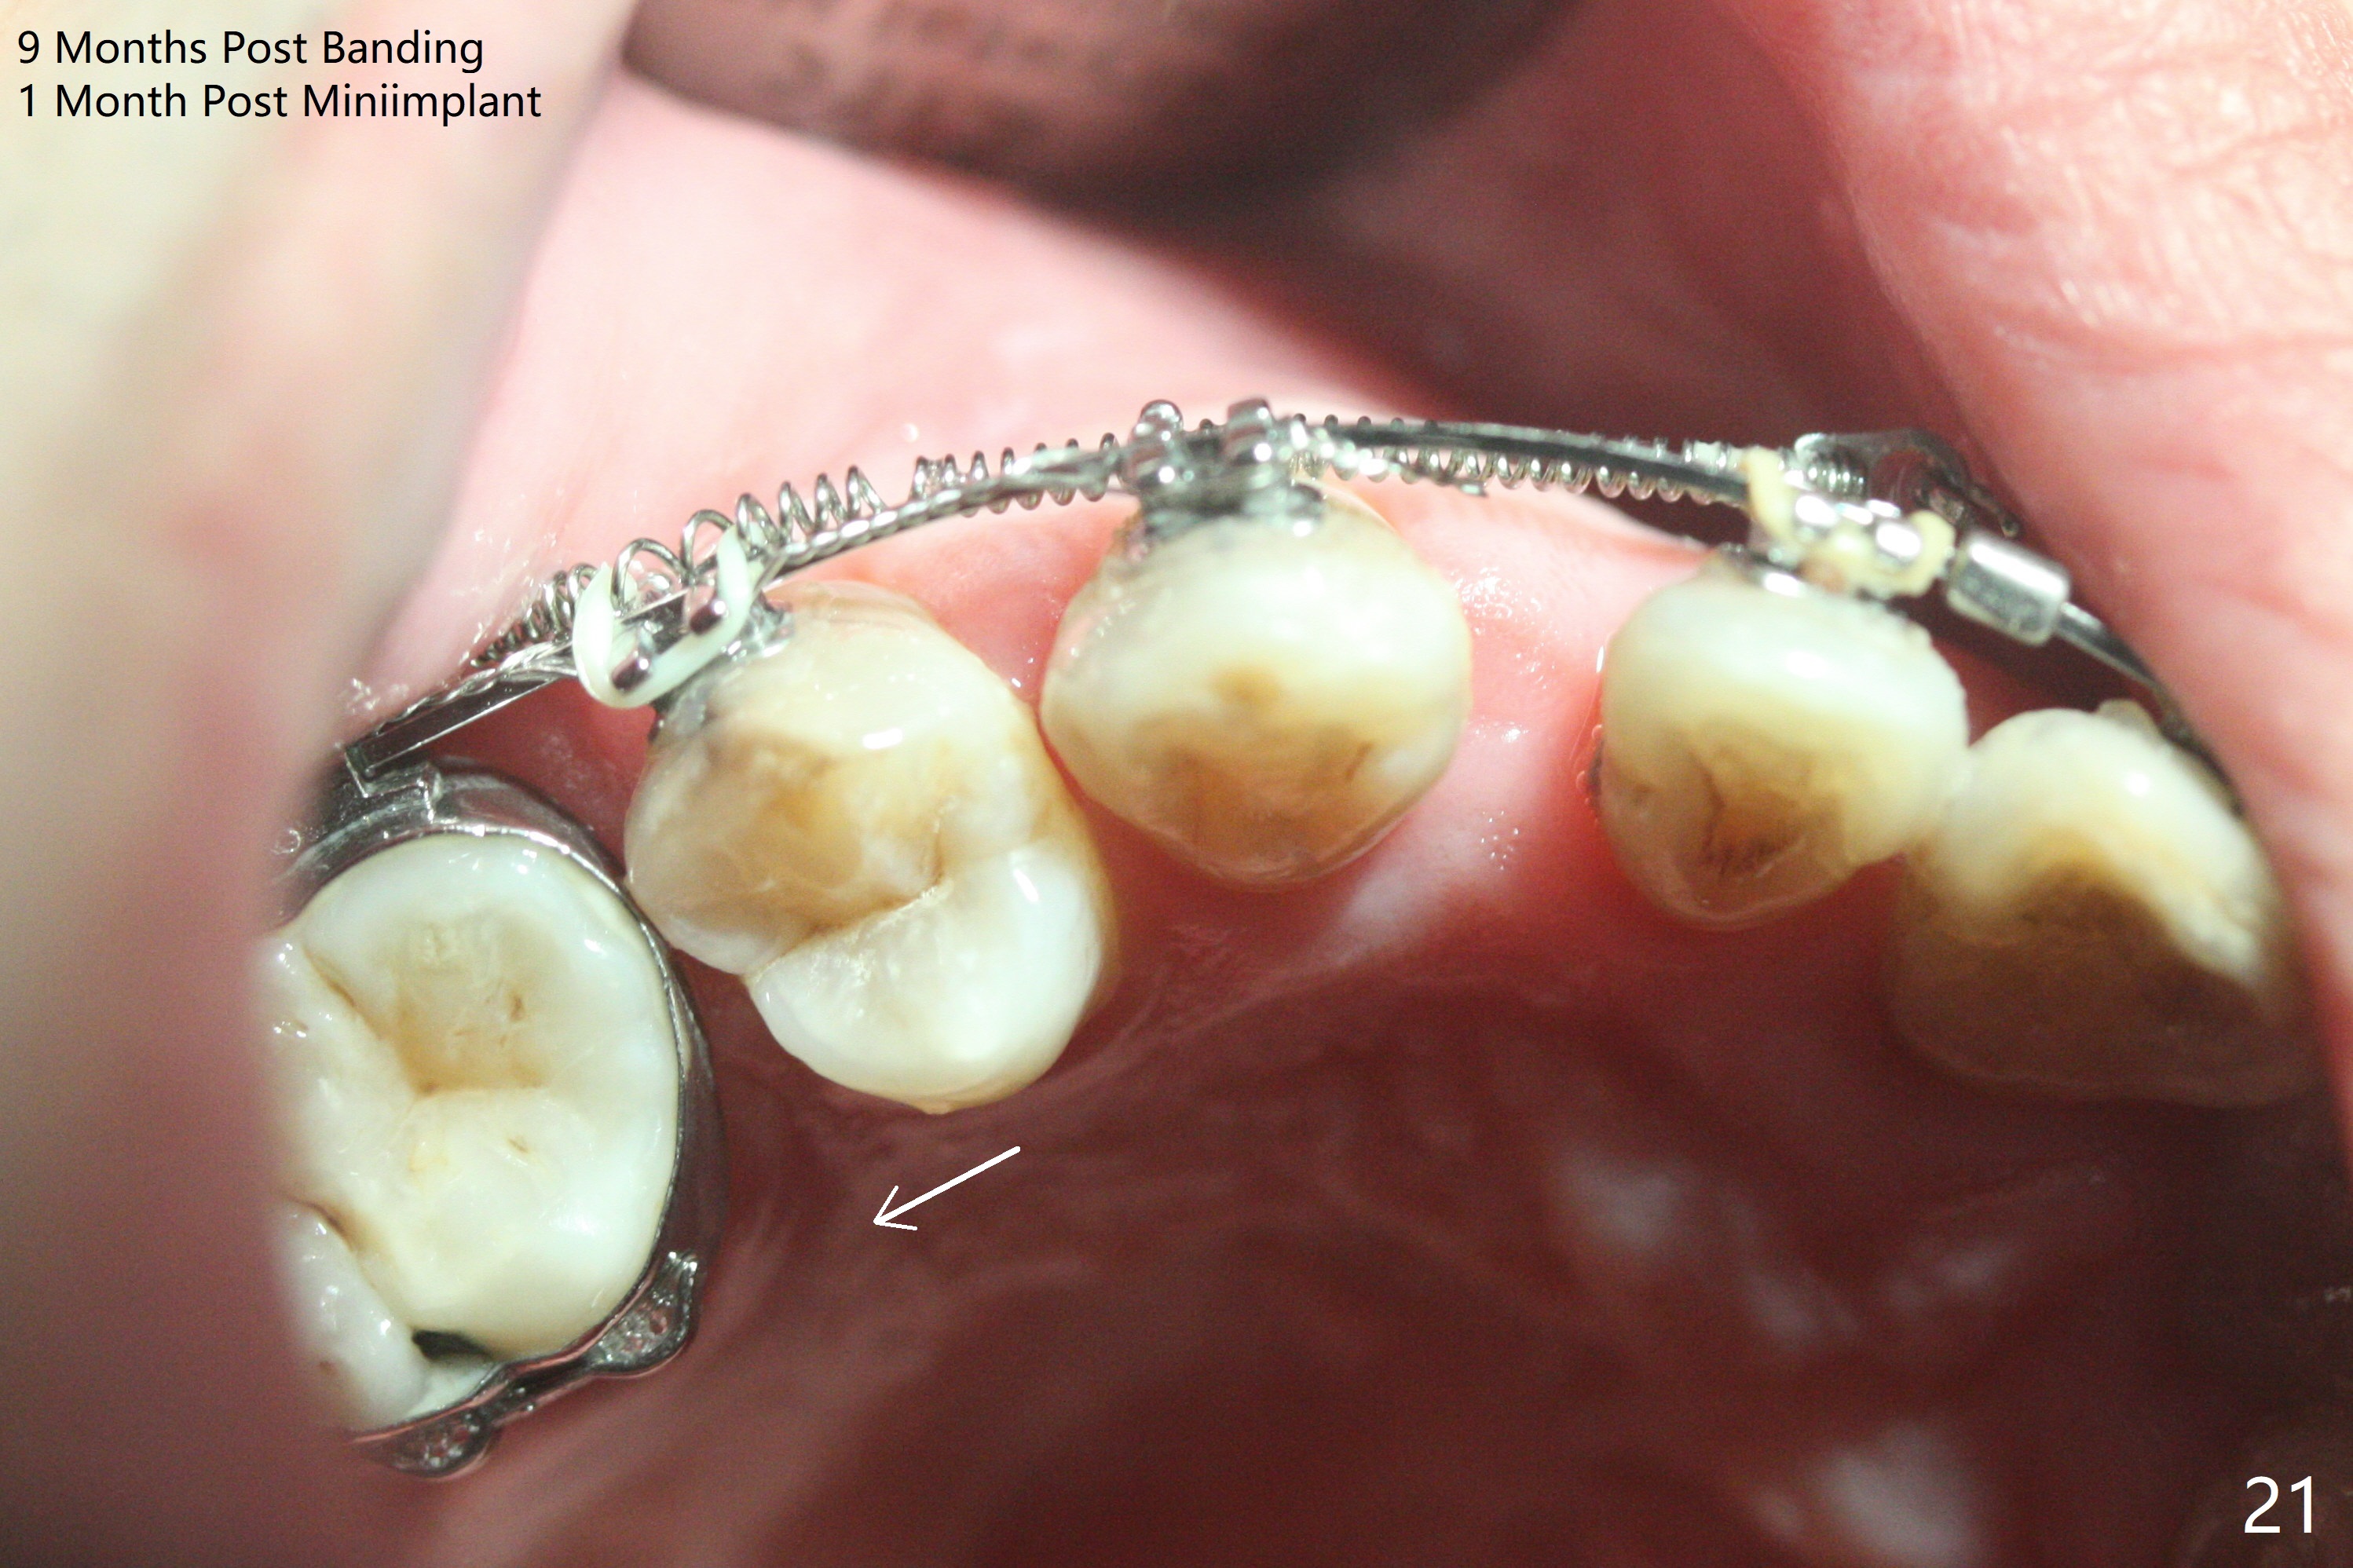

A 40-year-old man requests orthodontics after #17 and 32 extraction. UL5 is missing (Fig.1), while the upper midline deviates to the left (Fig.2 arrow) with crowding between UL2 and 3 (Fig.3). The main goal is to retract UL5 distal and move the upper midline to the right to alleviate UL anterior crowding. Implant will be not needed. To monitor potential root resorption associated with tooth movement, preop PAs are taken (Fig.4-7). The space for an implant at UR5 is narrow. UR4 needs to be distalized using UR7 or a miniimplant distal to UR7 as an anchor (Fig.8). UR4 and 3 will be repositioned to establish Class I occlusion (Fig.9). The space gained by UR4 distalization may be enough to correct the upper midline deviation and UL3 malposition (Fig.10). Brackets will be placed in the lower arch in spite of the normal alignment (Fig.11). UL2 and 3 brackets are unable to be engaged to 14 niti wire (Fig.12). Next visit try to engage UL2 bracket. If not, save the old wire for possible future reuse. Closed spring is placed with 18 ss wire <3 months post banding (coronavirus). Three weeks post closed spring between UR4-7, UR3,4 are being distalized (Fig.13). Distalization of UR4 is not much in 5.5 months (Fig.14,15). It seems necessary to use a miniimplant distal to UR7 as an anchor (Fig.16 white circle), place a long hook mesial to UL4 (more or less root movement instead of tilt) and place the same closed spring between the anchor and hook. In spite of the fact that UR4 seems to have been completely distalized and that UR2 is being distalized 8 months post banding (Fig.18), a 8 mm long mini-implant is placed in the maxillary tuberosity with minimal local anesthetic (Fig.17,19). A longer closed spring (18 mm) is placed between the implant and UR3 hook (Fig.20). Next appointment a lingual button will be placed at UR4 for rotation, while a post hook mesial to UR3 for torque. UR3 distalizes with the help of UR mini-implant, which is unfortunately loose. Next visit place lingual button at UR4 (Fig.21 arrow) to distalize the lingual cusp. Crimpable power hook is placed mesial to UR2 for distalization (for root torque, Fig.22). If it works, remove the wire and reposition the hook for UR1 next visit. UR2 is distalized in one appointment (~ 1 month, Fig.23, as compared to Fig.22). With lingual button at UR4, rotation seems to have been corrected shortly (Fig.24 arrow).